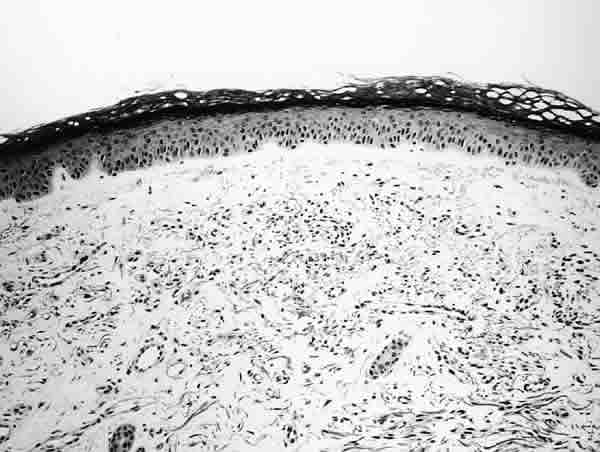

Fig. 2. Zona "granz" subepidérmica respetada por la proliferación vascular. Hematoxilina-eosina (x100).